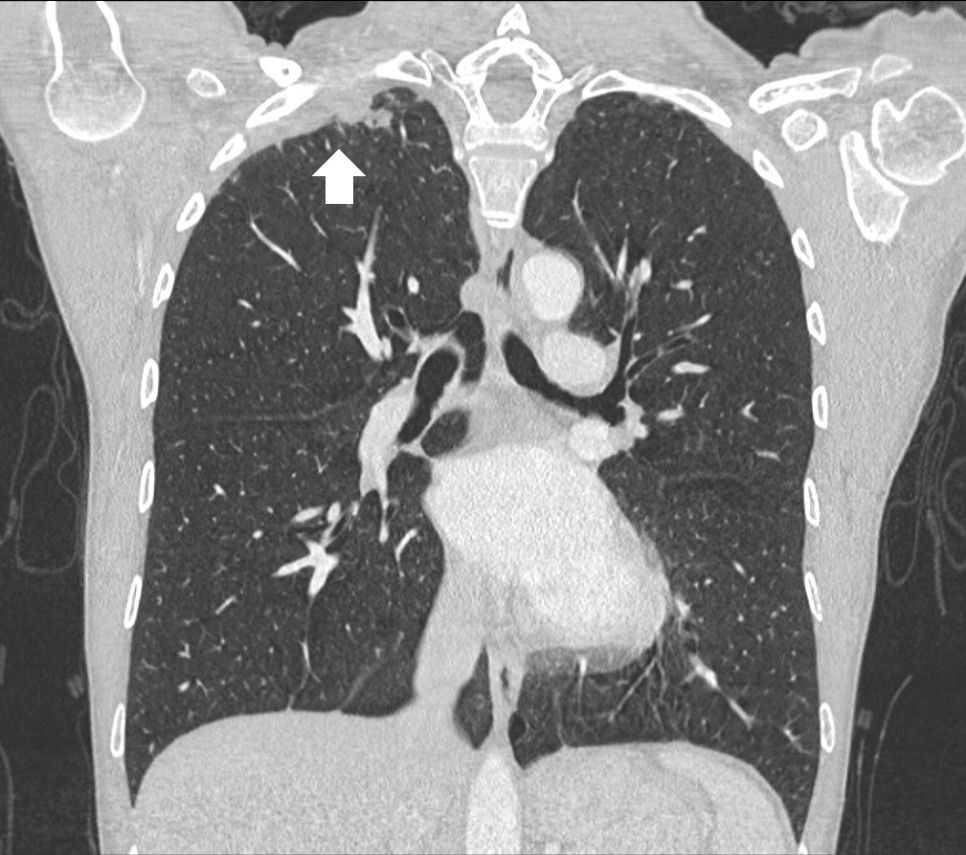

견갑배신경 포착에 대한 침구치료, 부항치료, 약침치료, 경추 교정 등으로 증상이 완화되었다 할 지라도 만약 다시 통증이 재발되고, 증상이 악화되는 경향이 있다면 드물지만 악성질환의 가능성도 염두에 둡시다. 저에게는 뼈에 사무치는 임상에서의 경험입니다. 원래 등 통증은 폐의 내장연관통이 나타나는 부위이고도 하지만 상구종양이라고도 불리는 폐첨부의 판코스트 종양(pancost tumor)에서는 경추 8번 신경이나 흉추 1, 2번 신경을 압박하여 목디스크와 유사한 통증을 유발하기에 근골격계성 통증이나 신경통으로 오인됩니다. 사실 근골격계를 주로 살피는 정형외과의, 재활의학과의, 그리고 일부 한의들의 경우 이런 악성질환의 가능성은 놓치기 되게 쉽습니다. 폐암의 경우 초기에 무증상인 경우가 많고 신경통 양상만이 유일한 증상으로 나타나는 경우가 있습니다. 1차 임상에서 경솔하게 판코스트 종양을 의심하기가 결코 쉽지 않지만, 체중이 빠진다거나 너무나 일반적인 경과와 다르게 병기가 진행된다면 한번쯤 전신 검사도 받게 하셔서 내장 문제를 배제할 필요가 있겠습니다.